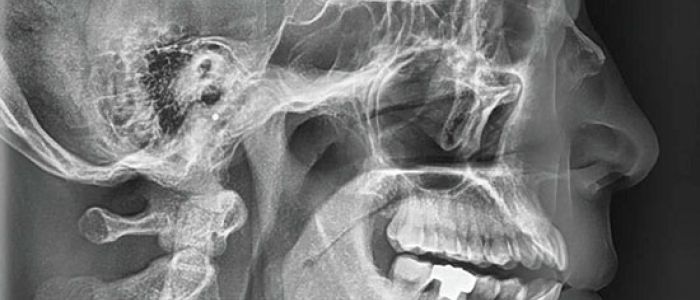

Radiografías Extraorales

Las radiografías extraorales se emplean cuando no es factible obtener información diagnóstica adecuada en las series de radiografías intraorales, es así que son utilizadas para observar un área grande de los maxilares y del cráneo en una sola radiografía. Los exámenes radiográficos extrabucales tienen el propósito de evaluar áreas grandes del cráneo, dientes impactados y patrones de erupción, crecimiento y desarrollo; examinar la extensión de lesiones grandes, traumatismos, articulación temporomandibular. Son de mucha utilidad principalmente en Ortodoncia y Cirugía Bucal.

Existen varias radiografías extraorales entre las cuales se tiene: